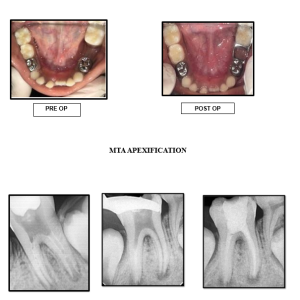

• Apexification and apexogenesis

• Regenerative Endodontic procedures